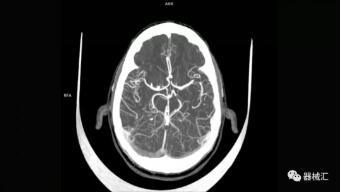

▲ SOMATOM On.site圖像